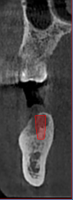

根管和牙周治疗过程中,提供牙根位置、角度、是否牙裂病变及下颌管、牙周围组织高清图像,以便于分辨治疗每个细节,做出精确诊断以及有效治疗方案。